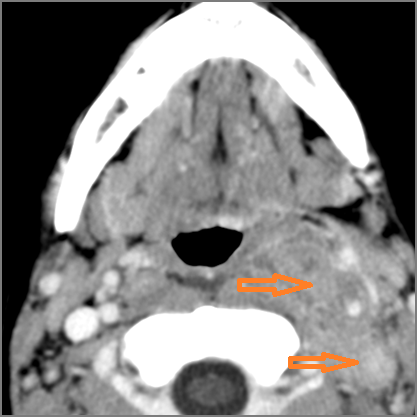

There is edema/abscess within the adjacent deep neck, and/or retropharyngeal space.